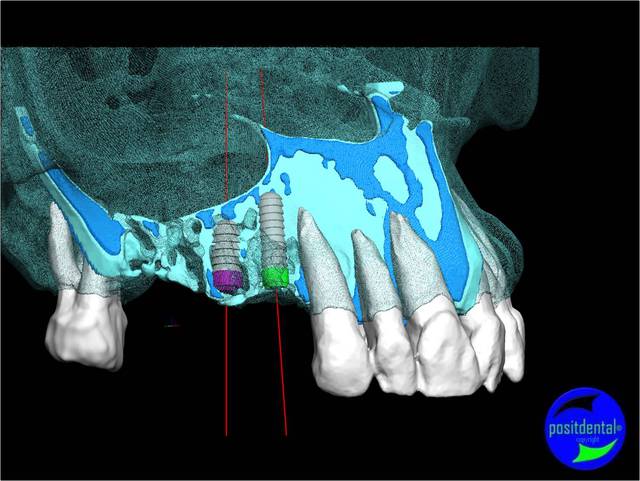

- la planification implantaire en 3D

Cas clinique n° 2

Positionner l'implant le mieux adapté, virtuellement, au meilleur endroit possible en tenant compte des contraintes anatomiques et de la future prothèse.